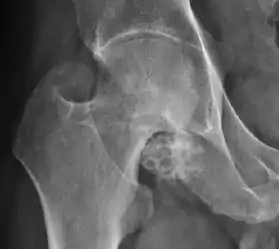

Synovial chondromatosis can be confidently diagnosed by X-ray when calcified cartilaginous chondromas are seen. However, other synovial proliferative processes, such as pigmented villonodular synovitis, require MRI for accurate diagnosis, although noncalcified synovitis can be suspected in radiographs by indirect signs, such as soft tissue swelling and/or erosions in the femoral head, femoral neck, or acetabulum (Figure 7).[1]

Figure 7:

X-ray of synovial chondromatosis.[1]

CT of synovial chondromatosis.[1]